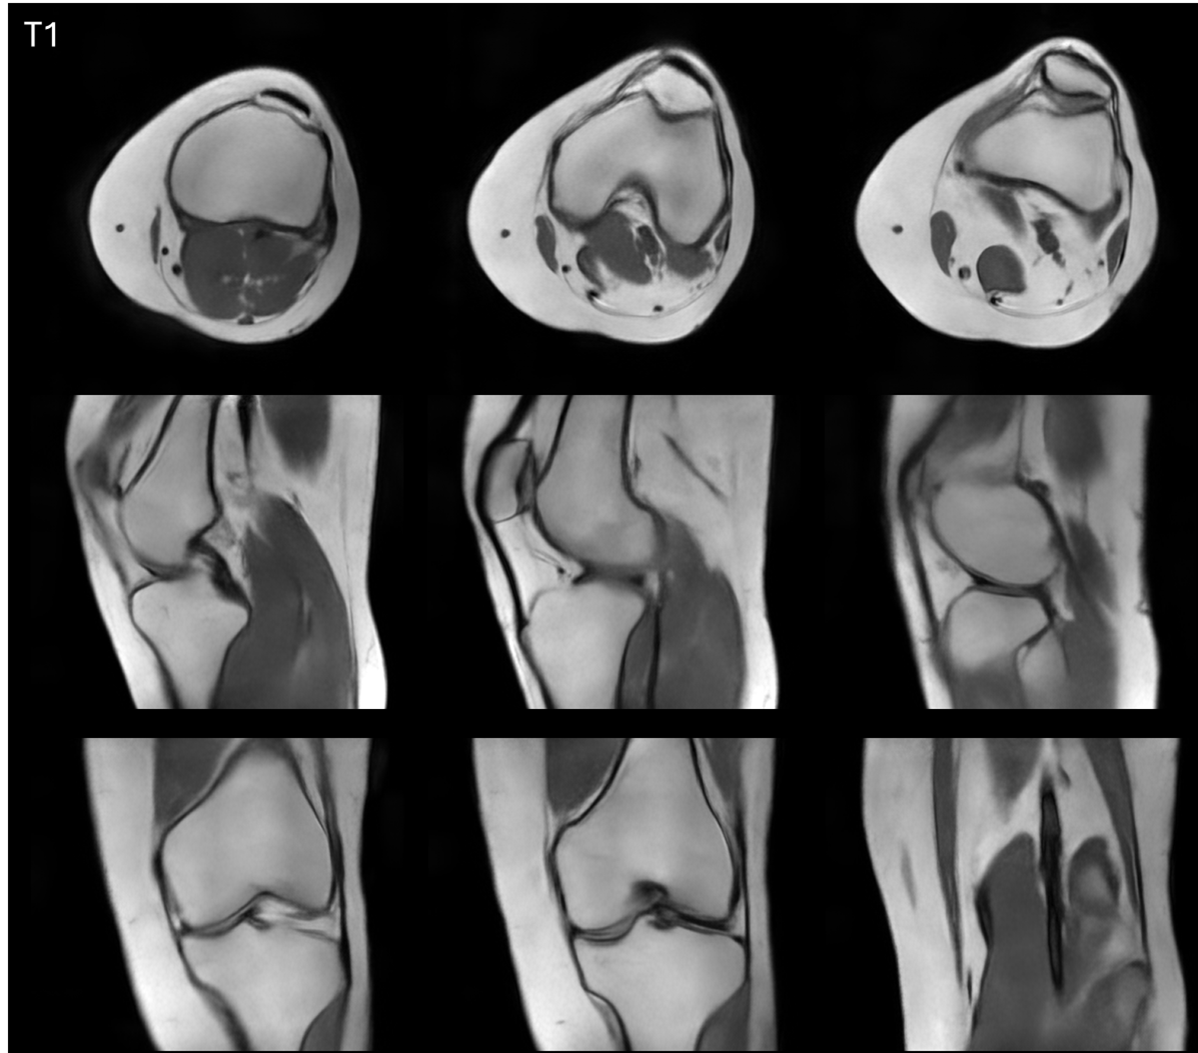

Knee Image

Clear visualization of ligaments, menisci, and articular cartilage enables accurate diagnosis of traumatic injuries and degenerative conditions. The system’s portable nature allows point-of-care imaging for sports medicine applications.